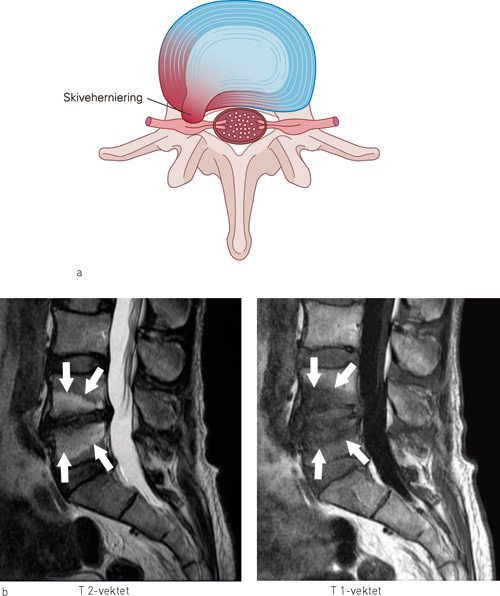

Modic-forandringer deles inn i tre kategorier/stadier (12). Modic type 1-forandringer (hypointense på T1-vektede og hyperintense på T2-vektede MR-bilder) representerer histopatologisk sett fissurerte endeplater, vaskularisert fibrøst vev i tilstøtende beinmarg og ødemer (fig 1). Modic type 2-forandringer (hyperintense på T1-vektede og isointense eller hyperintense på T2-vektede MR-bilder) representerer fissurerte endeplater og fettavleiring i subkondral beinmarg. Modic type 3-forandringer (hypointense både på T1- og T2-vektede MR-bilder) representerer subkondral beinsklerose.